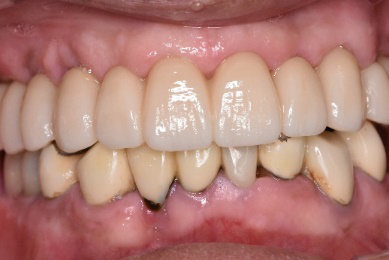

After

女性Mさん 40代(インプラント)

主訴

右上2本(第1第2小臼歯)の虫歯を治したい。

治療内容

レントゲンで詳しく診てみると、虫歯が歯根のほうまで進行し、保存することができないことがわかり、抜歯しました。抜歯後、骨が大きく欠損していましたので、骨造成を行いインプラントを2本埋入しました。

所感

抜歯後の欠損したところを補う方法には、部分入れ歯、ブリッジ、インプラントがあることを説明したところ、自分の歯と同じような感覚で嚙むことができるインプラントを選択されました。この方は、2016年に右下にインプラント治療をし、インプラントの良さを十分に理解しておられましたので、今回も2本歯を失ったところにインプラント治療を希望されました。今回もX-Guideを使った埋入で、安心安全に行うことできました。